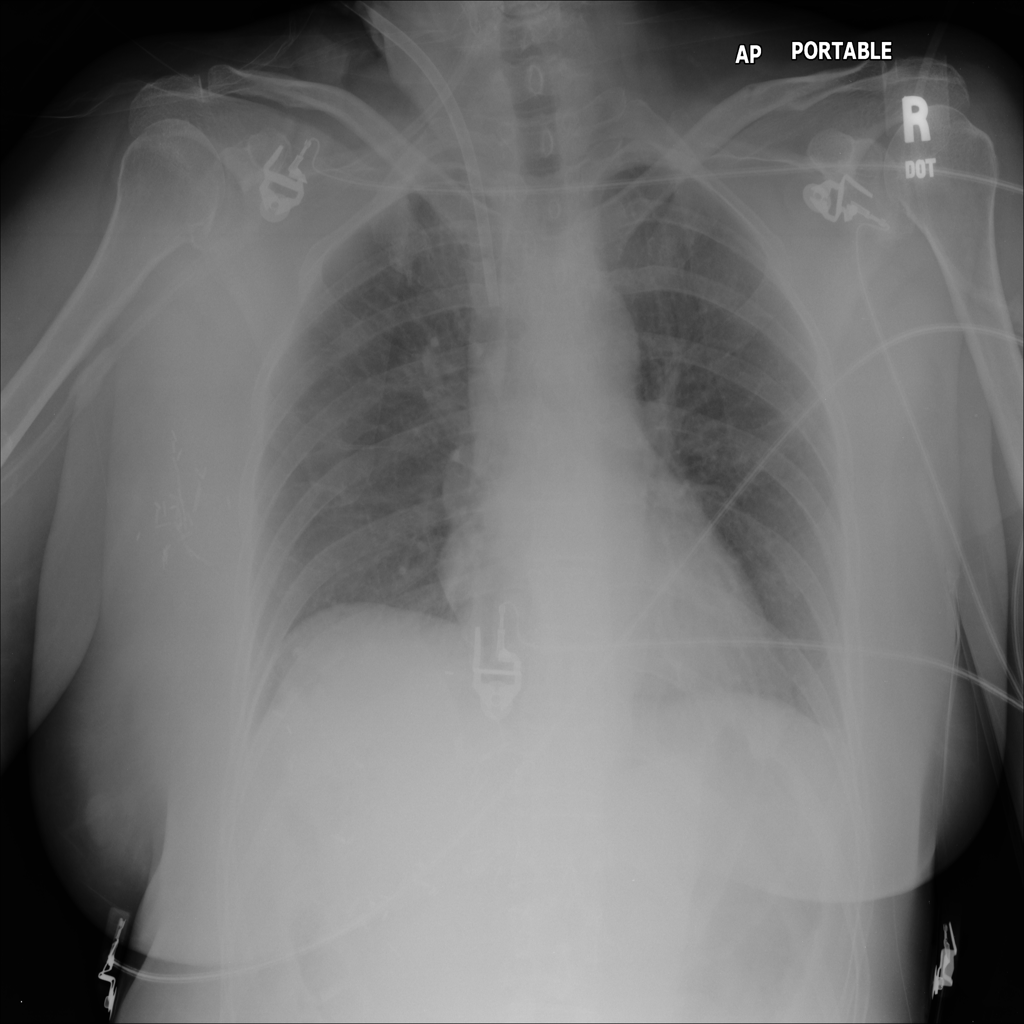

PAT-E81B · IMG-000Effusion

PAT-E81B · IMG-000

PA